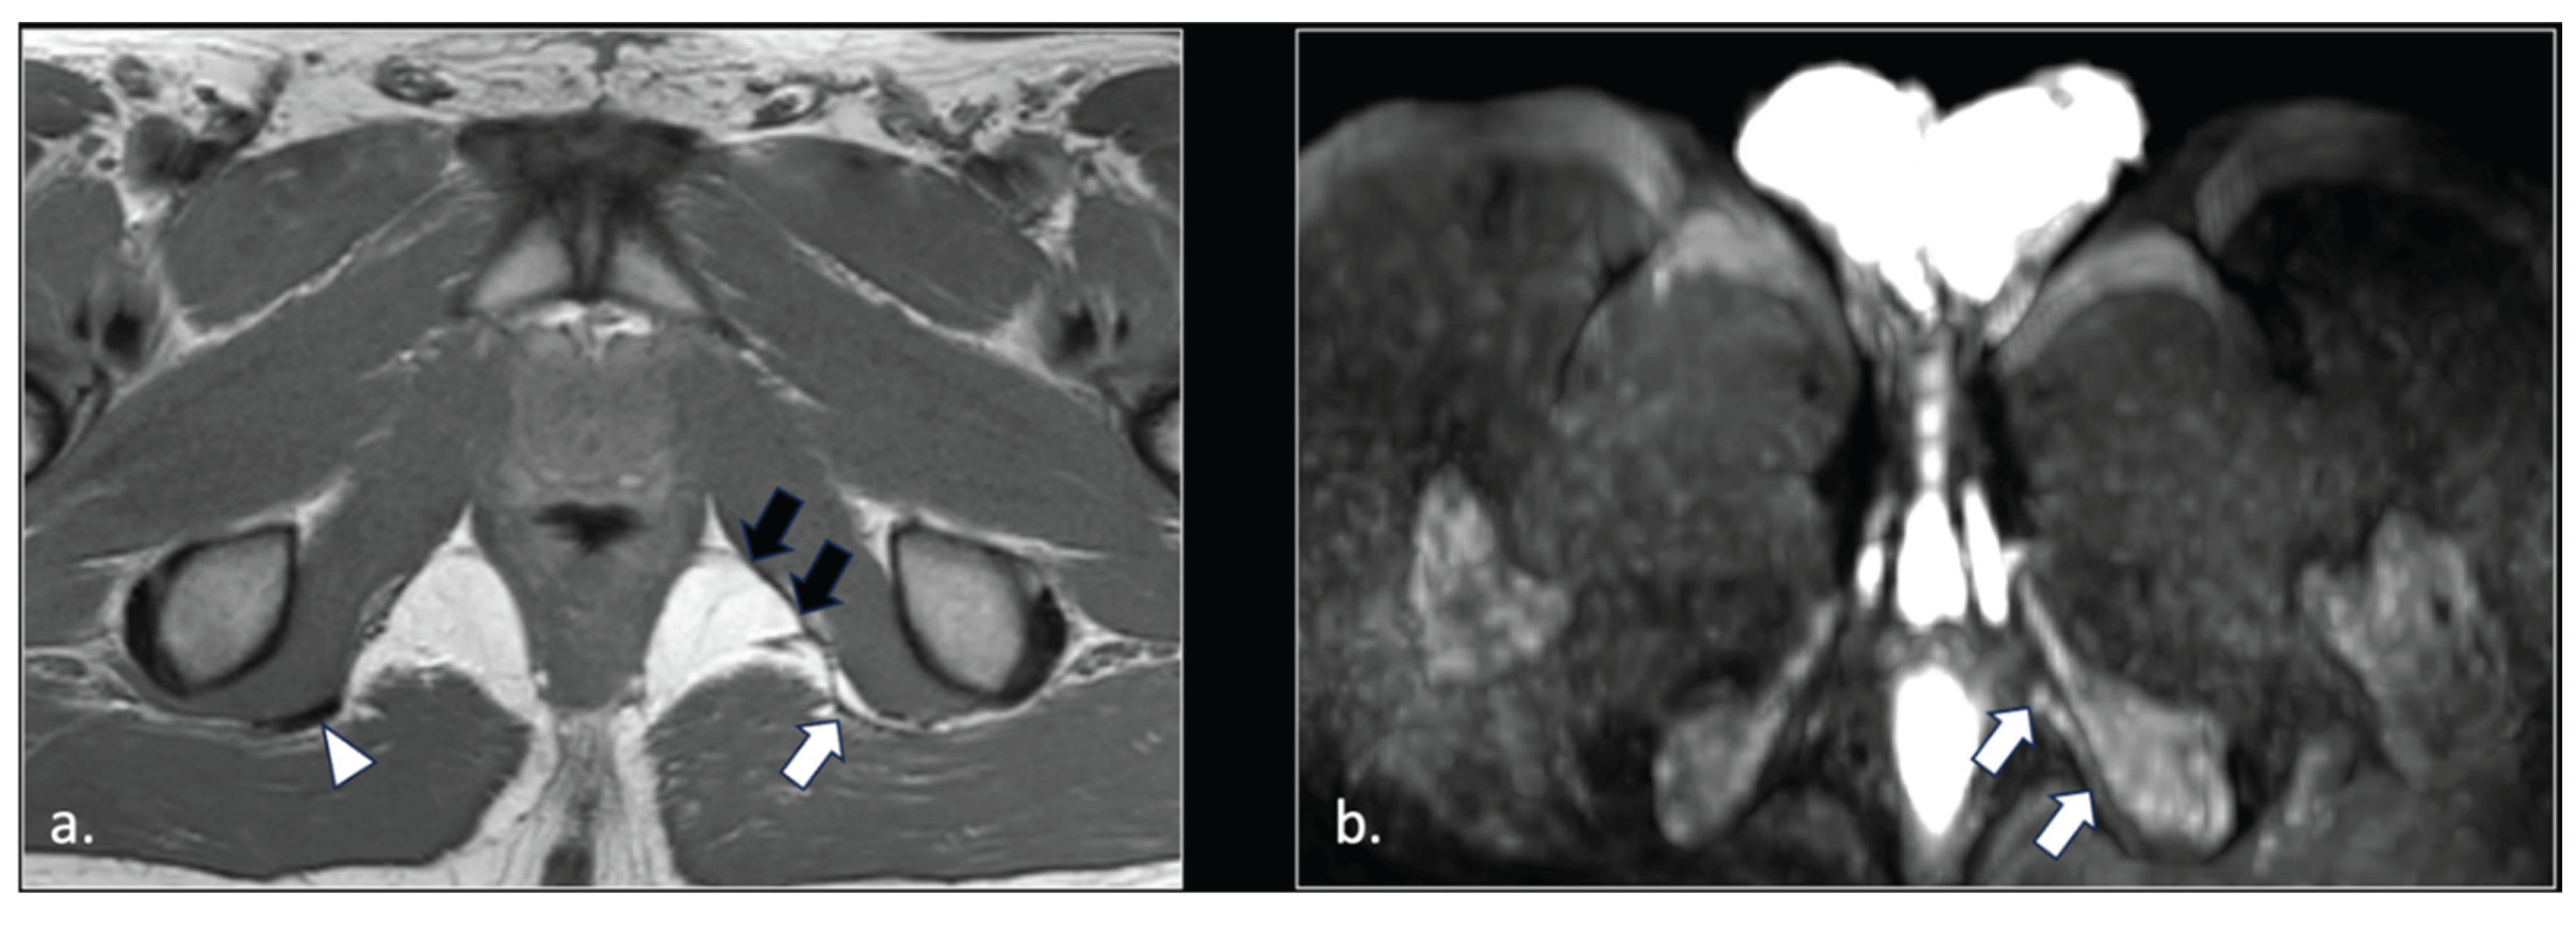

Figure 6.

43-years-old female with chronic post-traumatic pudendalgia. (a) Axial T2-weighted scan shows a normal right side pubo-coccygeus muscle (*). On the left side, an avulsion of the pubo-coccygeus muscle can be seen. The residual left pubo-coccygeus muscle is thinned (arrow). The vagina in shifted on the left side (**). (b) Axial b600 DWI scan demonstrates diffuse hyperintensity of the left pudendal nerve (arrow).